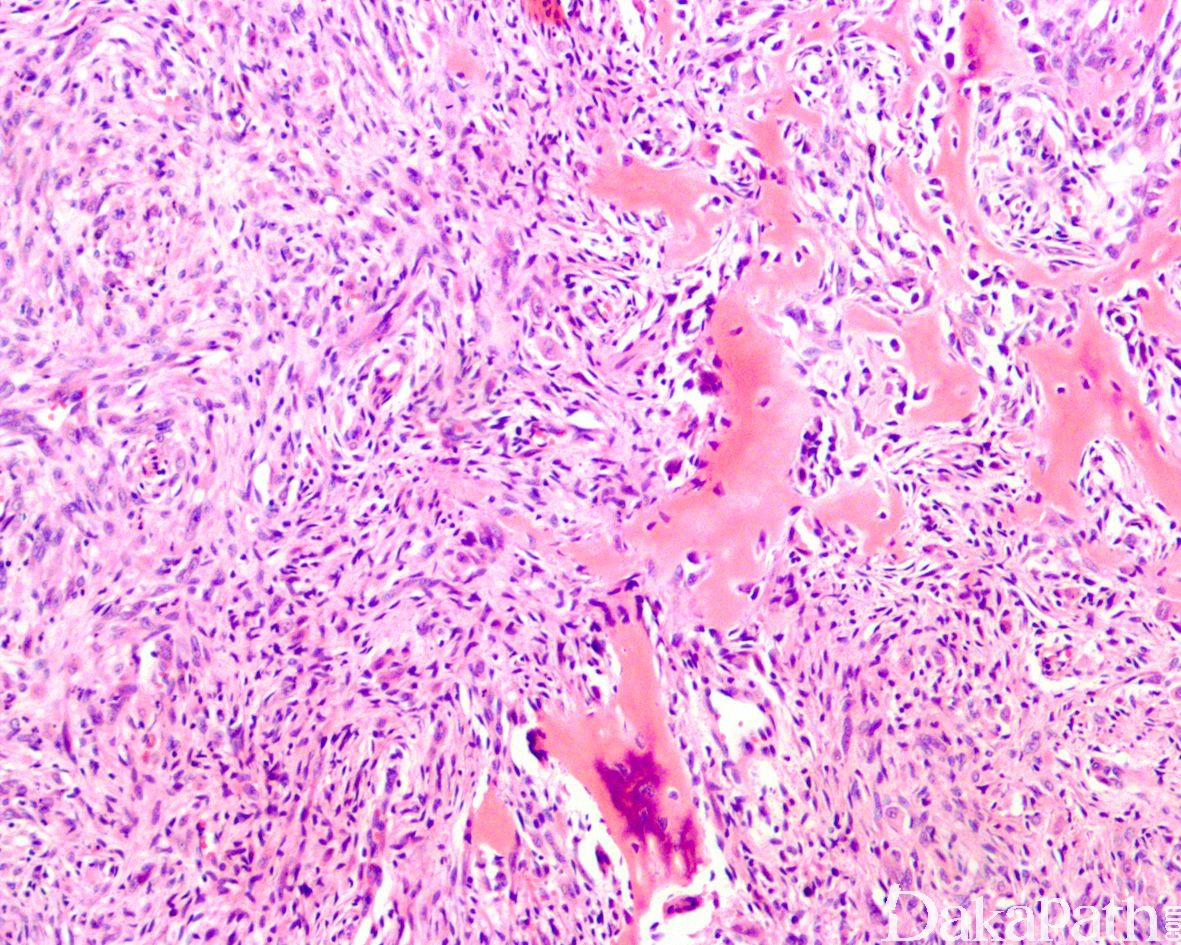

3. 肿瘤细胞呈密集片状或不规则束状或丛状排列浸润至皮下脂肪组织和肌肉组织内;

4. 瘤细胞胖梭形,部分呈上皮样,具丰富的嗜酸性胞质;

6. 无明显血管腔或出血,偶见局部的胞浆空泡提示血管内皮细胞分化;

10. 部分可见血管浸润和神经累犯;